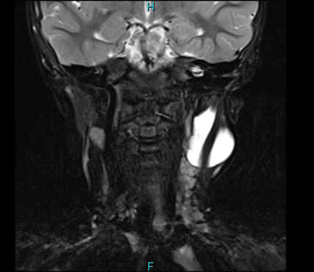

これも生まれつき持っている袋の病気です。正中頸嚢胞や、側頸嚢胞と異なり、1つの袋状ではなく、内部に壁を伴った、2つ以上の袋が集まったような形をしていることもよくあります。内部にはリンパ液がたまっています。

これも胎生期に、リンパ管という管が作られる際に、リンパ管が膨れたり、小さいリンパ管が集まって、袋のような柔らかい腫瘤をつくります。

また体中のいろいろな場所にできますが、特にくびにできたものは大きくなると気管を圧迫し、呼吸がしにくくなり危険なことがあります。このような場合は手術で摘出することになります。ただし、形がいびつなことも多く完全摘出がなかなか難しいこともあります。